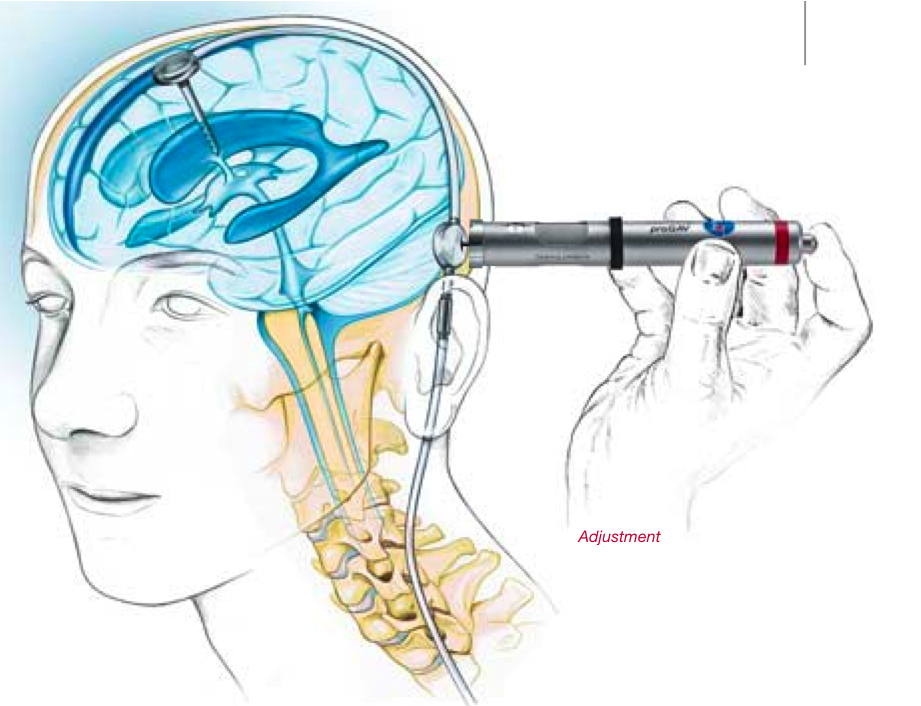

Вентрикуло-перитонеальный шунт: Показания и применение

Раздел: Фотоальбом решений